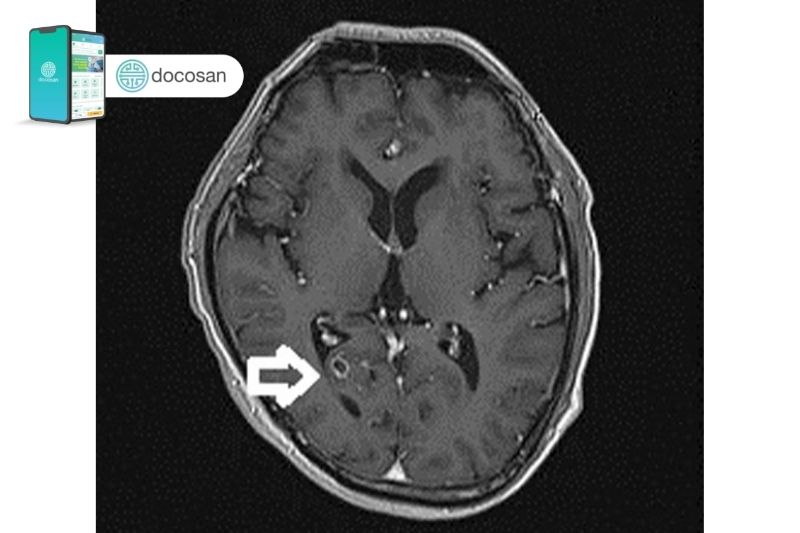

Một số kỹ thuật cận lâm sàng như chụp cắt lớp (CT scan) hoặc cộng hưởng từ (MRI) của não có thể giúp xác định việc có nang ấu trùng sán trong não hay không và đánh giá mức độ tổn thương do chúng gây ra.

Xét nghiệm phân để tìm trứng sán hoặc đốt sán mang trứng trong phân có thể được thực hiện trong trường hợp nghi ngờ nhưng chưa có bằng chứng xác thực. Tìm trứng sán bằng phương pháp Graham là một trong những phương pháp hữu hiệu. Sau đó, bác sĩ có thể chỉ định các cận lâm sàng khác như chụp X – quang, siêu âm, CT-scan hoặc thậm chí là MRI trong trường hợp bệnh nhân bị sán não. Do bệnh nhân bị sán não đến với bác sĩ trong hầu hết các tình huống đã bị thay đổi ý thức nên việc tiếp cận thường khá khó khăn.